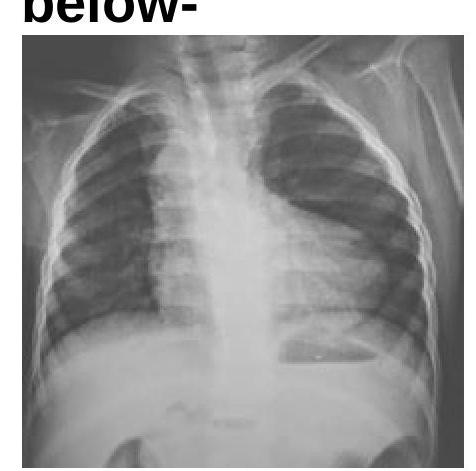

Identify the condition in the X-ray given below:

Explanation: ***TOF*** - The chest X-ray shows a **boot-shaped heart (coeur en sabot)**, which is highly characteristic of **Tetralogy of Fallot** due to right ventricular hypertrophy and pulmonary artery hypoplasia. - There is also **reduced pulmonary vascular markings** (oligemia), indicating decreased blood flow to the lungs, a typical finding in TOF. *TGA* - Transposition of the Great Arteries (TGA) typically presents with a **"egg-on-a-string" appearance** on chest X-ray, characterized by a narrow mediastinum and cardiomegaly, which is not seen here. - Pulmonary vascularity can be increased or normal in TGA, unlike the decreased vascularity observed in the image. *TAPVC* - Total Anomalous Pulmonary Venous Connection (TAPVC) usually shows a **"snowman" or "figure-of-8" heart** shadow on chest X-ray, due to enlarged SVC and innominate vein. - This condition is also associated with **increased pulmonary vascular markings** and often cardiomegaly, which are absent in the provided image. *Ebstein's anomaly* - Ebstein's anomaly is characterized by a **massively enlarged heart** on chest X-ray due to right atrial enlargement and tricuspid regurgitation. - It often shows **reduced pulmonary vascular markings** due to functional pulmonary stenosis, but the characteristic "boot shape" is not typically present.